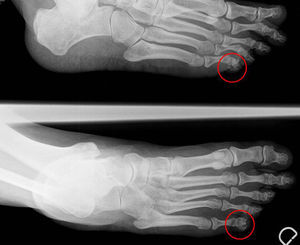

The patient was a 57-year-old woman who practiced hiking, and had no history of disease. She presented with a subcutaneous lesion measuring 5mm in the fifth toe of her left foot that she had detected 12 weeks earlier. The lesion was intensely painful and had undergone no changes. Plain radiography of the foot revealed the presence of a small calcification on the lateral border of the distal phalanx of the fifth toe on left foot (Fig. 1). Analyses included inflammatory markers, calcium, phosphorus and uric acid, which were all normal. The pain disappeared after extirpation (Fig. 2). In 20 months of follow-up, it has not reappeared.